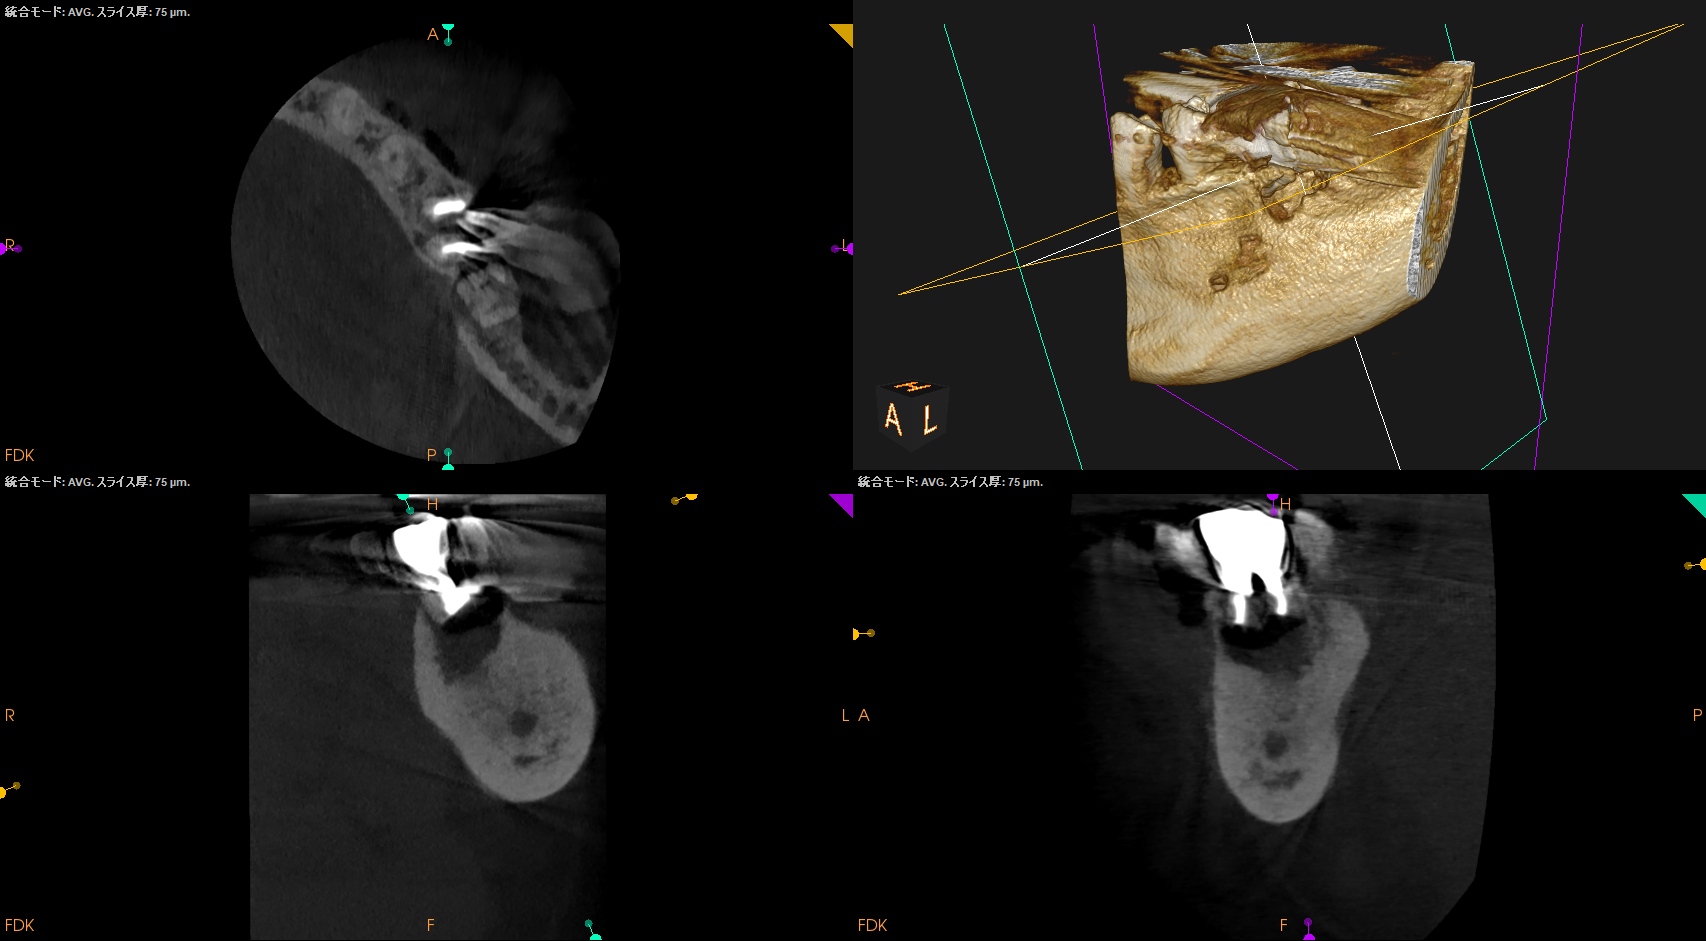

CBCT(2024.9.12)

MB

ML

D

治療はApicoectomyだ。

しかもM,Dともにである。